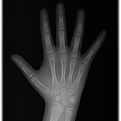

Radiografia palmar

A radiografia da mão e punho, possibilita determinar a idade óssea do paciente.